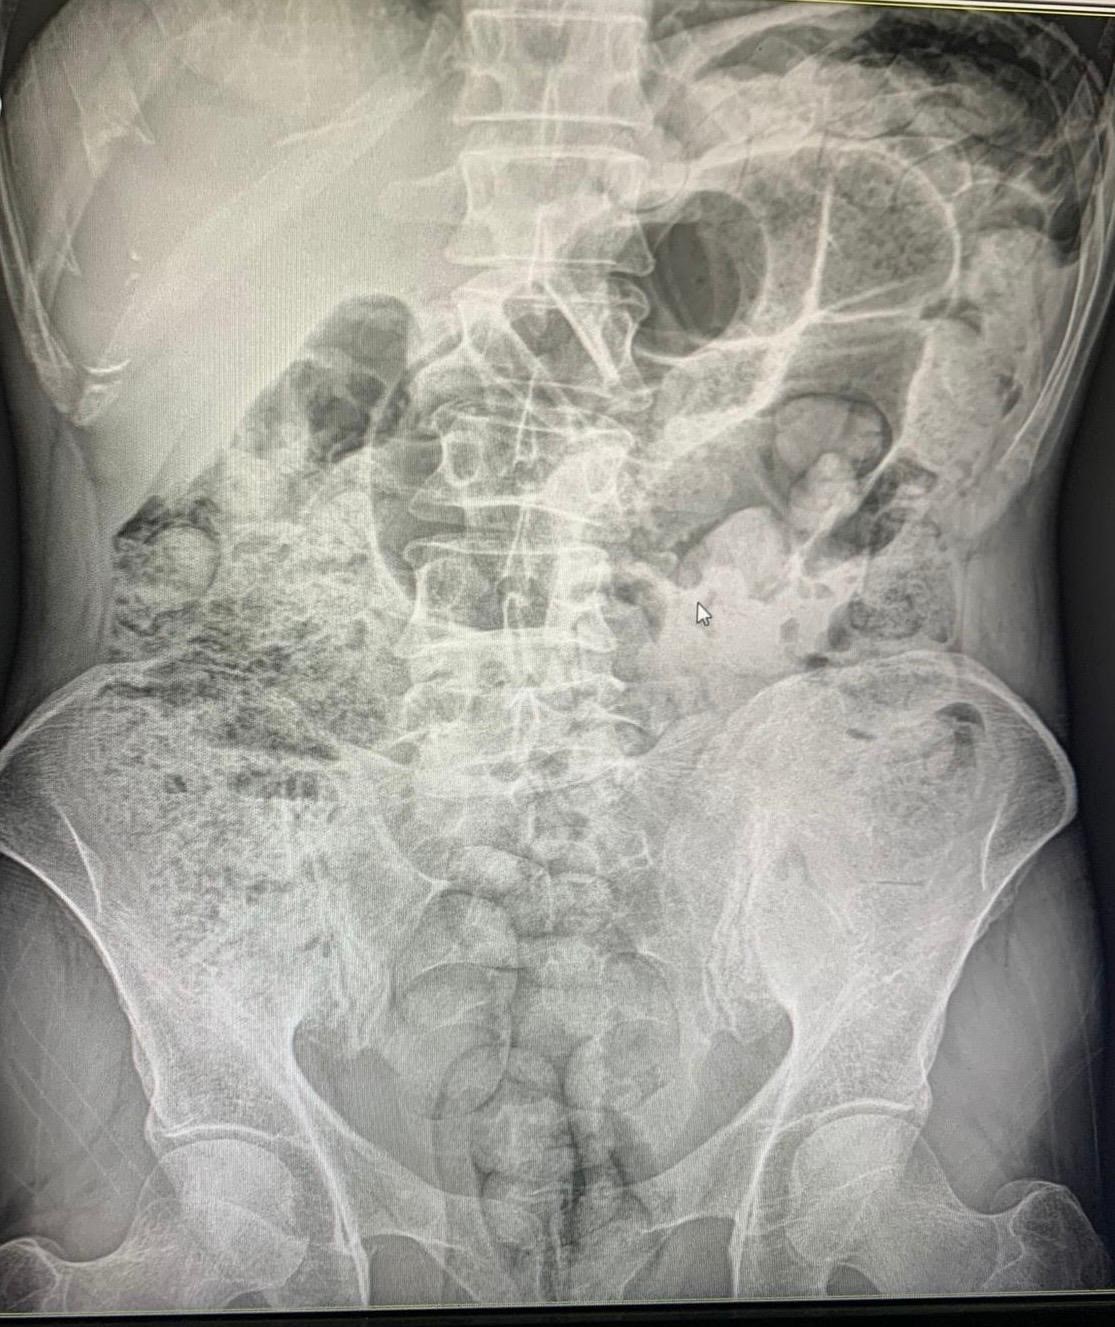

Siirt Emniyet Müdürlüğü Narkotik Suçlarla Mücadele Şube Müdürlüğü görevlilerince 14 Aralıkta Baykan Şehit Bünyamin Torgut Polis Uygulama Noktasında durdurulan iki araçta, batı illerine uyuşturucu madde sevk etmek için uyuşturucu maddeleri özel yöntemler kullanarak paketleyerek yutmak yöntemiyle mide kısmında taşıyan İran uyruklu 3 kadın 1 erkek şahıs yakalanmıştı. Şahısların midelerinde bulunan uyuşturucu maddeler 10 gün devam eden hastane süreci sonucunda cerrahi yöntemler kullanılarak çıkartıldı.

Şüpheli şahısların midelerinden 119 paket halinde 1 kilo 597 gram uyuşturucu madde çıkartıldı. Zanlılar, sevk edildikleri adli makamlarca tutuklanarak cezaevine sevk edildi.